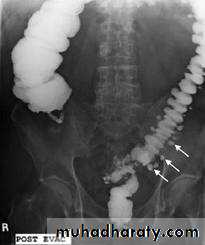

Familial Polyposis Syndromes

Autosomal dominant with high penetrance (80%)• About 2/3 of affected people have a positive family hx of colonic polyps or ca and about 1/3 are sporadic cases

• Colonic polyps are numerous and of all different sizes

• They may be sessile or pedunculated

• Rectum and left colon are more commonly affected than right side of colon

• Often, however, the entire colon is carpeted with polyps

accounts for 1 percent of all cases of colorectal cancer